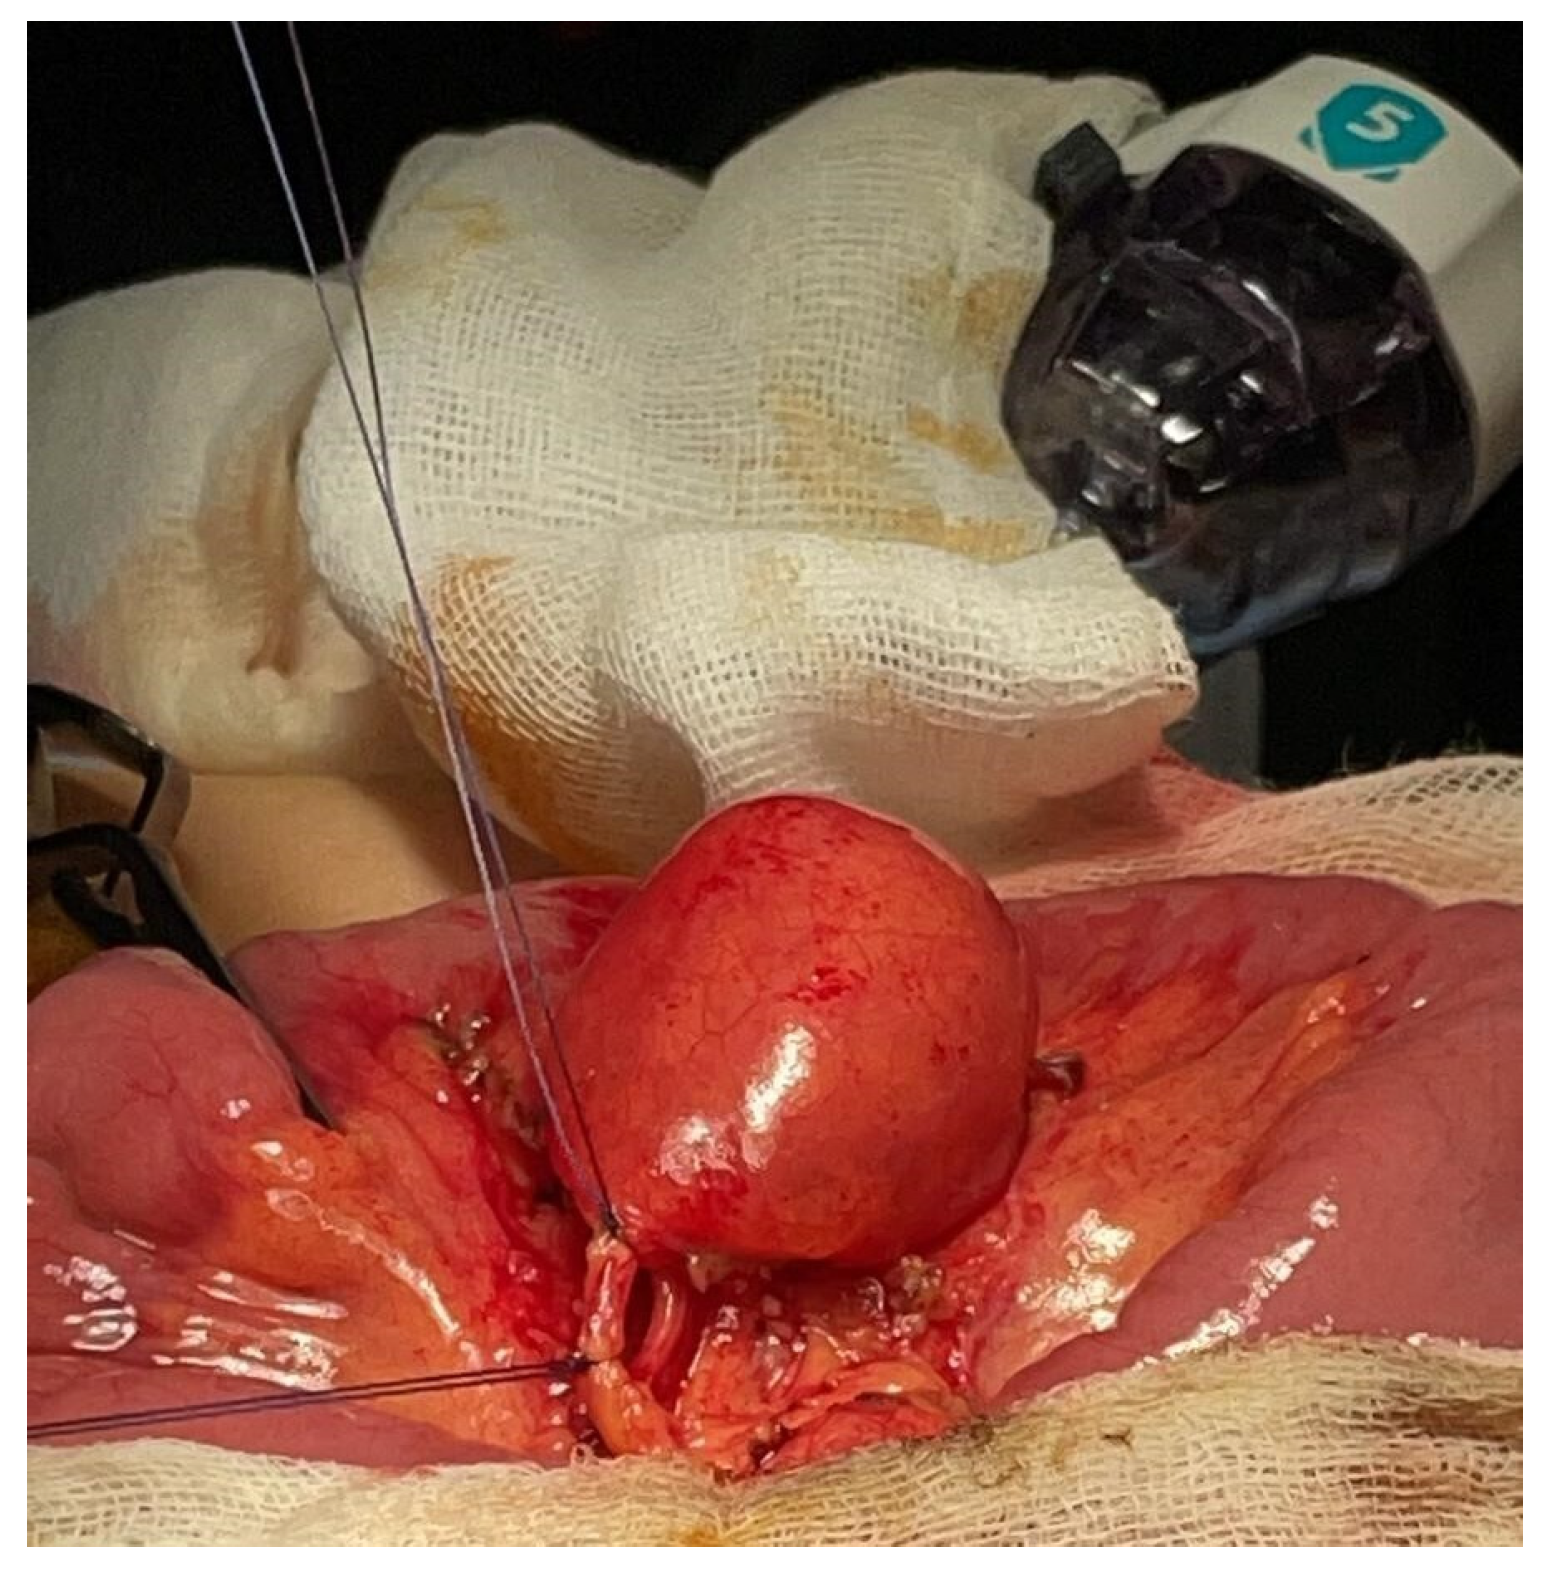

Figure 2.

Case 1—Intraoperative appearance of MMD.